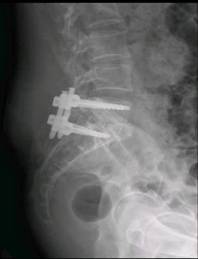

术后患者立即感到腰腿部不适明显缓解,术后24小时左右已在保护下站起,室内锻炼行走。术前症状几乎完全消失。术后复查X线片显示:腰5-骶1椎间隙高度较术前明显恢复,腰5椎体滑脱完全纠正,融合器位置理想。

术后复查腰椎正侧位

根据患者病情特点、主观诉求等实际情况,结合我科前期已成功为众多患者微创OLIF手术治疗腰椎管狭窄症的丰富经验,脊柱微创中心专家组为该患者制定“斜外侧入路腰5-骶1椎间隙融合(OLIF)+后路经皮置钉内固定手术”方案。手术由张银刚教授主刀,刘凯博士协助,手术历时2.5小时,手术顺利,出血不到50ml。